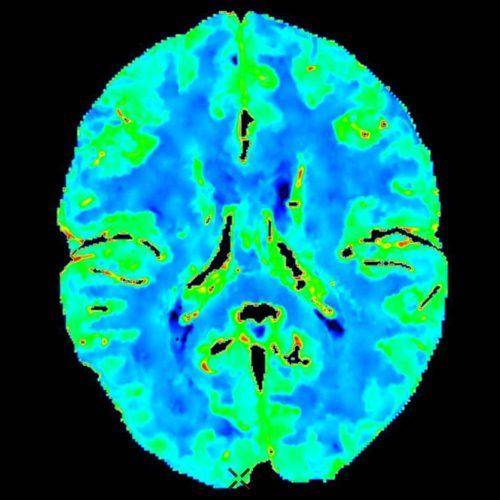

В результате проведения компьютерной томографии сосудов головного мозга получают их трехмерное изображение. Оно показывает детальную структуру, состояние ткани и движение крови. Для выполнения процедуры вводится контрастное вещество.

Этот метод предоставляет подробную информацию об особенностях кровообращения шеи и головного мозга. Отличие МРТ от классической и КТ-ангиографии головного мозга в том, что вместо рентгеновского излучения используется магнитное поле и радиочастотный импульс. Аппарат улавливает и регистрирует скорость кровотока, предоставляя двухмерные или трехмерные изображения.

При классической ангиографии изучаются рентгеновские снимки. Излучение проходит неравномерно, поэтому плотность отдельных тканей проявляется по-разному. Костные ткани представлены в белом цвете, мозг – в сером, ликвор и сосуды – в черном. При КТ и МРТ- ангиографии изучаются снимки в трехмерном виде.

На снимках проверяют отдельно очертания, форму каждого сосуда. Они должны быть ровными с равномерным изменением просвета. Обнаруженное сужение, нестандартные изгибы, ответвления, возникновение аномальных сосудов позволяет определить диагноз и терапию.